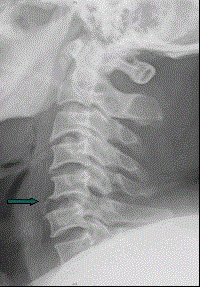

患者男,38岁,车祸伤后导致颈部疼痛、四肢瘫痪,排尿、粪失禁,ASIA分级C级,入院时间为伤后6 h,佩戴颈托入院。于急诊行颈椎正侧位X线片(如图)。...

问题 患者男,38岁,车祸伤后导致颈部疼痛、四肢瘫痪,排尿、粪失禁,ASIA分级C级,入院时间为伤后6 h,佩戴颈托入院。于急诊行颈椎正侧位X线片(如图)。 除了上消化道出血,应用大剂量MP的并发症还有(提示 经MP治疗后,患者出现黑粪。)